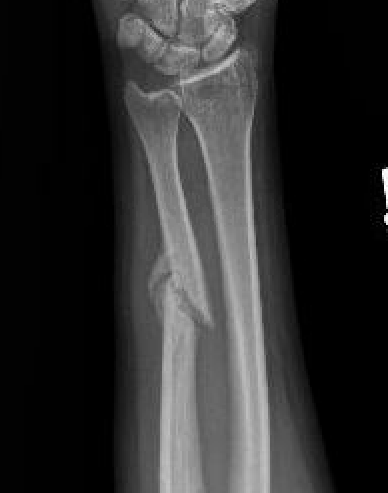

Mechanism

Night stick injury - direct blow or trauma to ulna

Nonoperative management

Indications

Minimally displaced fractures

- < 50% displaced

- < 10 degrees angulation